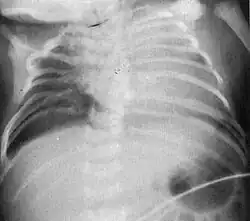

Radiograph depicting typical skeletal features of Jarcho-Levin syndrome, subtype spondylothoracic dysplasia. Note fanlike configuration of the ribs, with extensive posterior fusion, along with multiple vertebral segmentation defects.

Spondylothoracic dysplasia

Spondylothoracic dysplasia, or STD, has been repeatedly described as an autosomal recessively inherited condition that results in a characteristic fan-like configuration of the ribs with minimal intrinsic rib anomalies. Infants born with this condition typically died early in life due to recurrent respiratory infections and pneumonia due to their restricted thorax.[3][4][5] Recently, a report[6] has documented that actual mortality associated with STD is only about 50%, with many survivors leading healthy, independent lives.